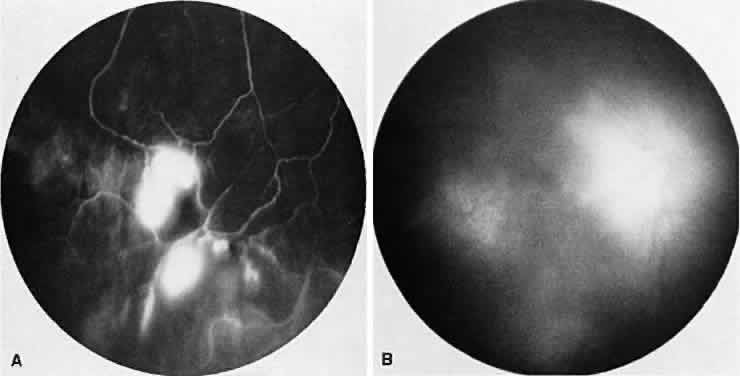

VOGT-KOYANAGI-HARADA SYNDROME

Vogt-Koyanagi-Harada syndrome, also known as uveomeningoencephalitis syndrome, is a systemic disease often found in young, darkly pigmented whites, blacks, native Indians, Hispanics, and Asians. It presents as an anterior and posterior uveitis with disc hyperemia, disc edema, and exudative retinal detachment (Figs. 2A and B and 3A). Systemic signs and symptoms include headache, hearing loss, poliosis, vitiligo, nuchal rigidity, seizures, and even coma. SRNV and disciform scars are late complications. The differential diagnosis should include AMPPPE and sympathetic ophthalmia.

Fig. 2. Vogt-Koyanagi-Harada syndrome. (A) Fundus photograph of the right eye and (B) the left eye showing bullous retinal detachments. (C) Fluorescein angiogram showing multiple hyperfluorescent leaks at the level of the retinal pigment epithelium. (D) Multiple coalescing leaks and fluorescein staining of the subretinal fluid. Large areas of hyperfluorescence involving the entire right posterior pole due to pooling of dye beneath the subretinal space.

Fig. 3. Vogt-Koyanagi-Harada syndrome. A. Fundus photograph of the left eye showing multifocal serous retinal detachment. B. Late fluorescein angiogram showing pooling of dye in the areas of serous detachment. C. Indocyanine angiography showing areas of blocked fluorescence corresponding to serous detachment. More areas of hypofluorescence are noted than those observed on fluorescein angiogram.

There is a characteristic fluorescein angiographic appearance in the early phase showing multiple discrete hyperfluorescent dots at the retinal pigment epithelial level that enlarge over time (see Fig. 2C and D). In the late phase, if there is a serous detachment, the fluorescein pools beneath the subretinal space (see Fig. 3B). The edematous disc hyperfluoresces in the late phase. Generally, the retinal vessels are unaffected.7,8 Retinochoroidal anastomoses also have been documented by fluorescein angiography.9

ICG angiography shows multiple hypofluorescent spots in the posterior pole (see Fig. 3C). These spots may coalesce and obscure the filling of large choroidal vessels. When serous retinal detachment develops, the marked hyperfluorescence observed on FA is not as prominently noted in ICG angiography, presumably because of the highly protein-bound nature of ICG. In fact, diffuse late hypofluorescence may be observed in patients with serous retinal detachment.10 Ill-defined areas of hyperfluorescence corresponding to diffuse choroidal staining may be seen in some cases in the late phases of the angiogram. The optic disc may stain with ICG in the acute phase but usually is minimal compared to that observed on FA.